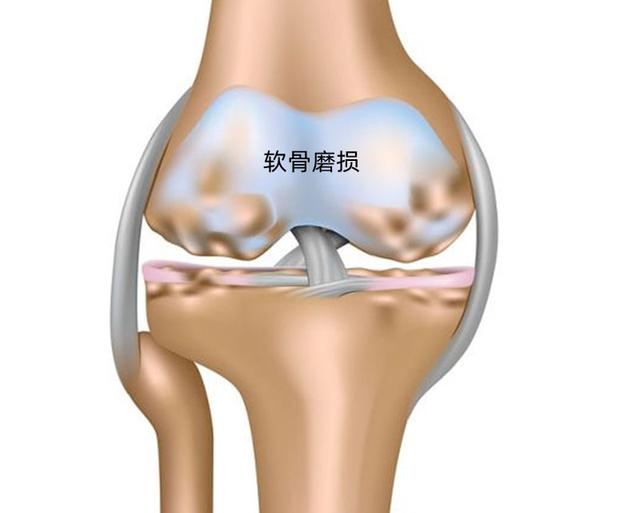

膝盖隐隐约约的疼,关节炎是怎么样个疼法?

走平路正常,下楼梯膝盖疼痛,究竟是什么问题?